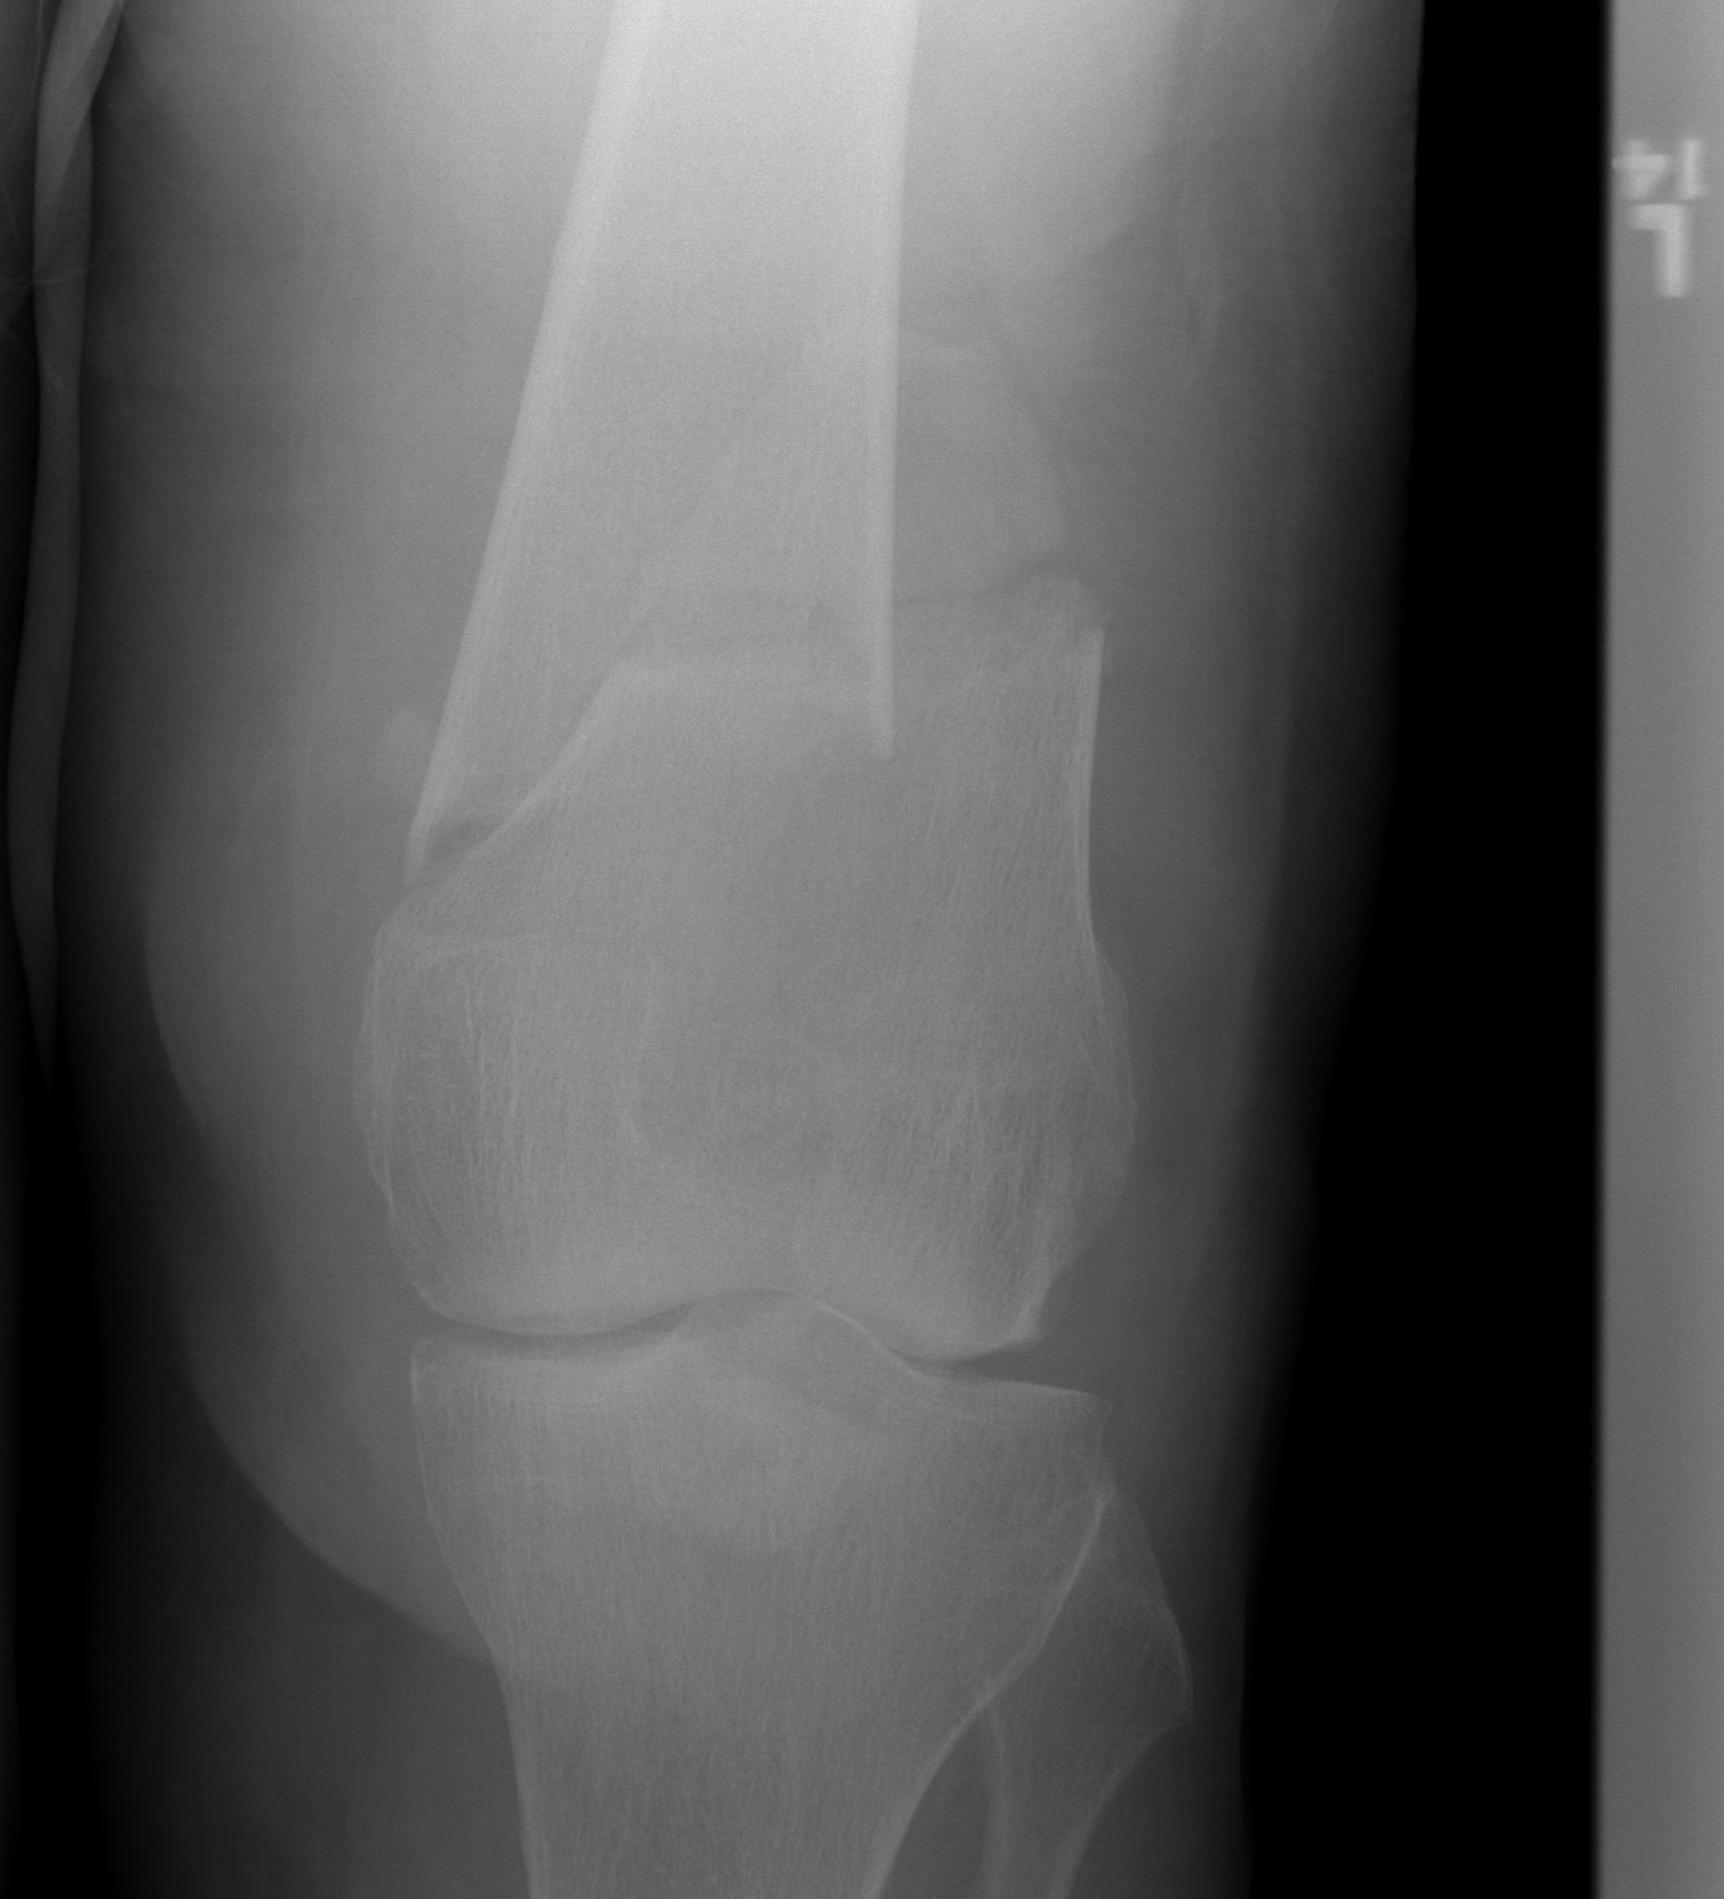

AO Type B1 & B2: Partial articular

![]()

Definition

Medial or lateral sagittal split

Technique

ORIF

- medial or lateral approach based on fracture location

- reduce articular split and fix with screws

- medial or lateral buttress plate

Lateral split fracture distal femur